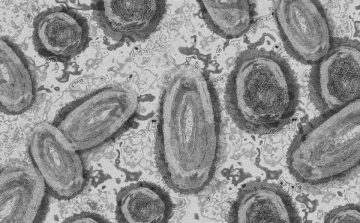

Tovább nőtt a majomhimlő-fertőzöttek száma Magyarországon

Újabb két embernél igazolt majomhimlő-fertőzést a Nemzeti Népegészségügyi Központ (NNK) a 33. héten - augusztus 15-től 21-ig -, ezzel 64-re nőtt a magyarországi esetek száma.